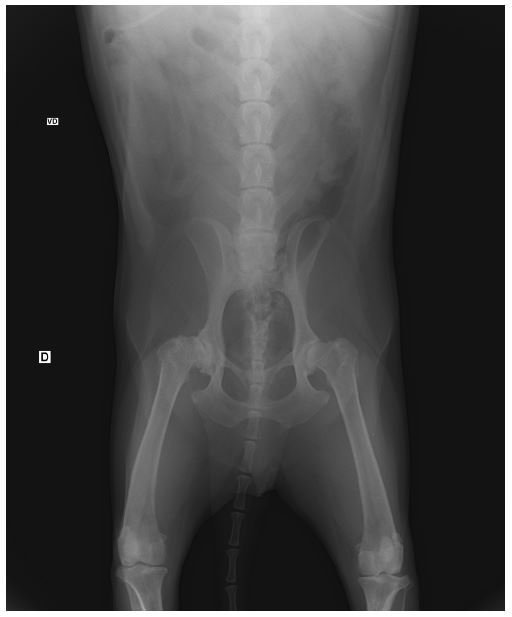

OPERAÇÃO

Os exames foram mostrados ao um veterinário ortopedista que concluiu que a melhor opção seria uma operação de denervação articular coxofemural. Valor total: R$4.500,00.

A Neospora é uma doença neuromuscular severa, leva a destruição de um número elevado de células neuronais. As céculas afetadas do Edie foram as que fazem ele ter equilibrio e faz ele andar. No momento 2019, a doença esta sendo controlada e se ele fizer fisioterapia pode voltar a andar :D